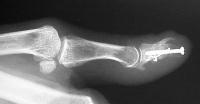

This incorporated, with some terminal resorption:

Click for larger image